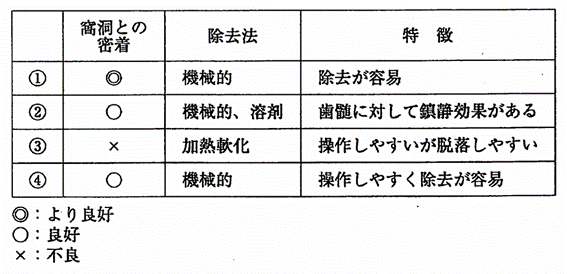

午前-94

仮封材の性質と特徴を表に示す。水硬性仮封材はどれか。1つ選べ。ただし、①~④は、酸化亜鉛ユージノールセメント、水硬性仮封材、テンポラリー ストッピング、レジン系仮封材のいずれかである。

a. ①

b. ②

c. ③

d. ④

解答を見る

a